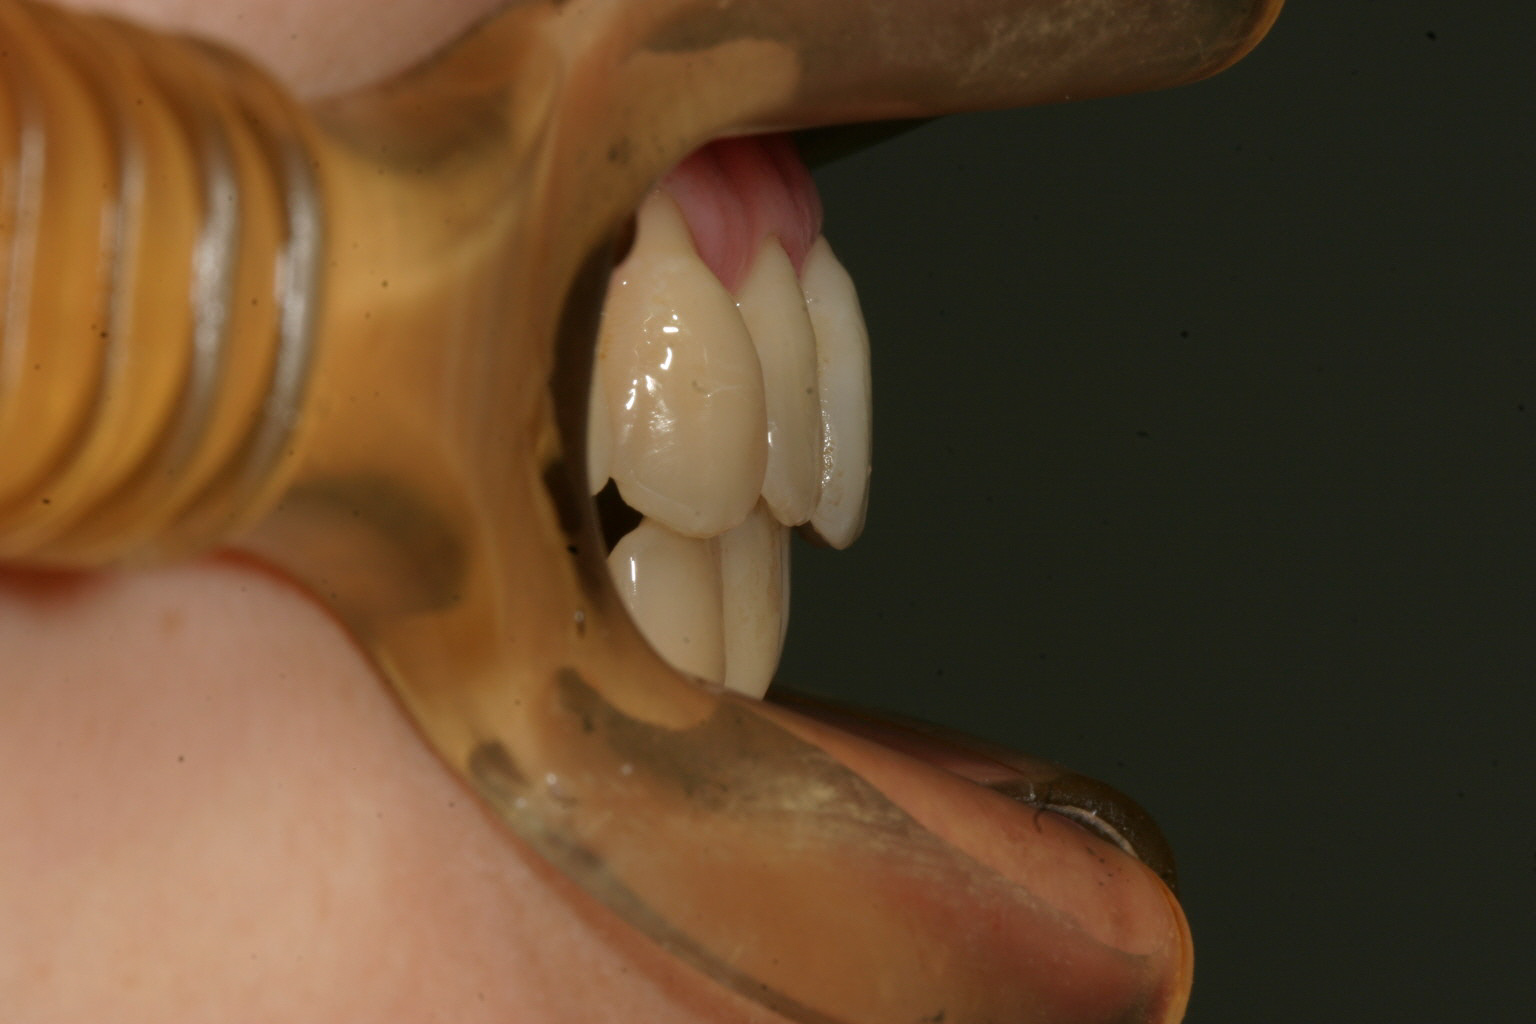

時間をかけてここまで改善しました。 最初と比べると別人の様です。

下顎もすごいでしょ!

前突感もきれいに治まりました。